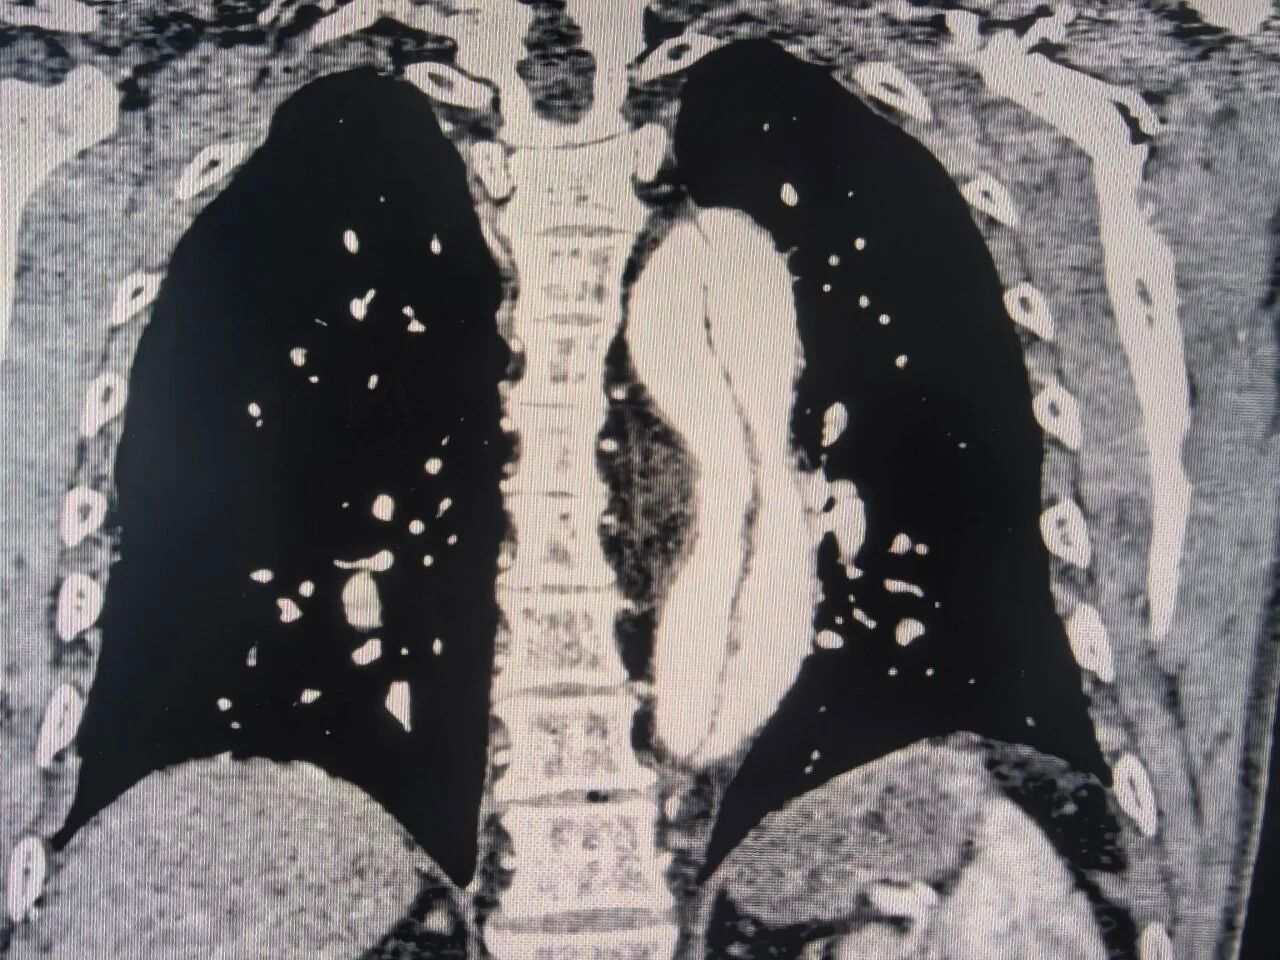

术前CT检查

这是一种极其凶险的血管疾病,主动脉内膜撕裂后,血液涌入血管壁中层,如同在体内形成一个随时可能破裂的“假腔”,一旦夹层破裂,患者将面临致命性大出血,生死只在顷刻之间。